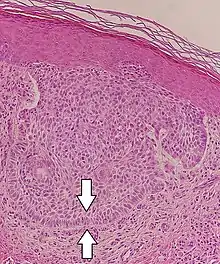

Differential diagnoses

Differential diagnosis | Pathological Features | Image |

---|---|---|

Hair follicles | Peripheral sections may look like nests, but do not display atypia, nuclei are smaller, and serial sections will reveal the rest of the hair follicle. | ![]() |

Squamous-cell carcinoma of the skin | Squamous-cell carcinoma of the skin is generally distinguishable by for example relatively more cytoplasm, horn cyst formation and absence of palisading and cleft formations. Yet, a high prevalence means a relatively high incidence of borderline cases, such as basal-cell carcinoma with squamous cell metaplasia (H&E stain at left in image). BerEP4 staining helps in such cases, staining only basal-cell carcinoma cells (right in image). | ![]() |

Trichoblastoma | Absence of cleft, rudimentary hair germs, papillary mesenchymal bodies. | ![]() |

Adenoid cystic carcinoma | Lack of basaloid cells disposed in peripheral palisades; adenoid-cystic lesion without connection to the epidermis; absence of artefactual clefts | ![]() |

Microcystic adnexal carcinoma | Bland keratinocytes, keratin cysts, ductal differentiation. BerEp4- (in 60% of cases),[24] CEA+, EMA+ | |

Trichoepithelioma[notes 1] | Rims of collagen bundles, calcification, follicular/sebaceous/infundibular differentiation and cut artefacts. Cytokeratin (CK)20+, p75+, Pleckstrin homology-like domain family A member 1 + (PHLDA1+), common acute lymphoblastic leukemiaantigen + (CD10+) in tumor stroma, CK 6-, Ki-67- and Androgen Rceptor- (AR-) | ![]() |

Merkel cell carcinoma | Cells arranged in a diffuse, trabecular and/or nested pattern, involving also the subcutis. Mouse Anti-Cytokeratin (CAM) 5.2+, CK20+, S100-, human leukocyte common antigen- ( LCA-), thyroid transcription factor 1- (TTF1-) | ![]() |